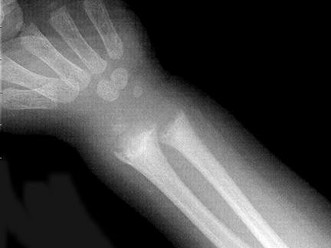

[单选题]男,10岁,有外伤,根据所提供图像,选择最佳选项 ( )A.未见异常B.骺移骨折C.青枝骨折D.腕关节脱位E.踝关节脱位